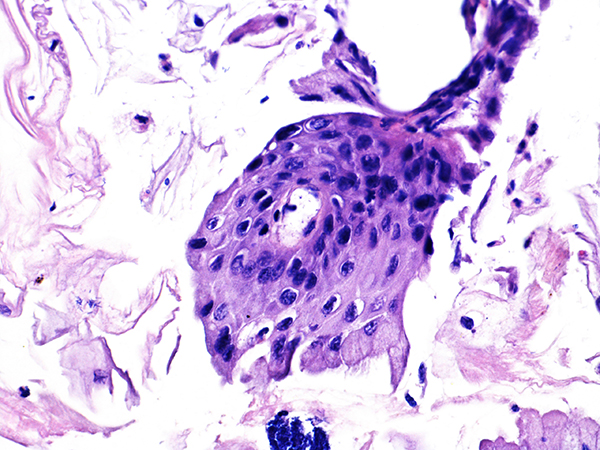

Area 1 - Soft Bx CIN 2 40x - High Power |

![]() Case 1